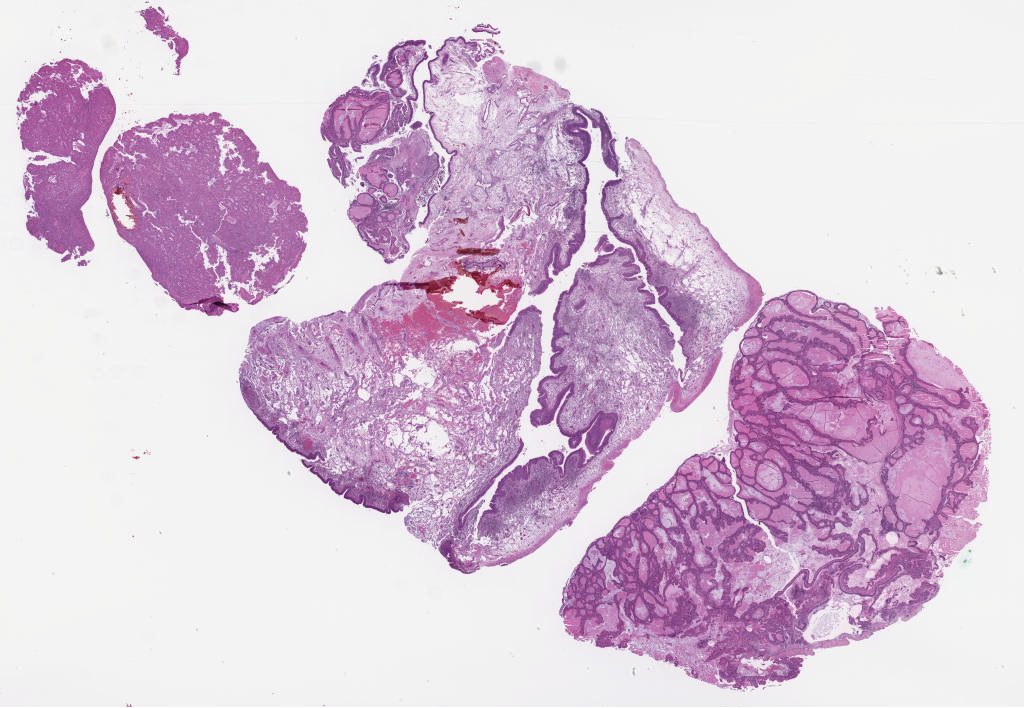

snac 2.svs

97608

x

73502

@

40X